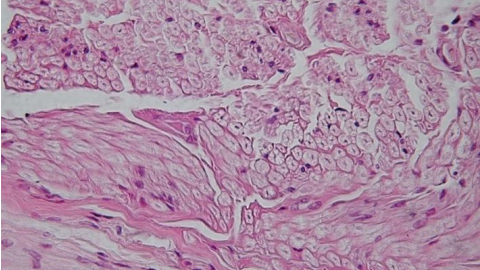

tessuto cellulare_wikipediaFirenze – Si chiama test HPV (Human Papillomavirus) ed è l’esame che sta sostituendo il Pap test come screening di controllo nelle donne over 33 anni in Toscana per la prevenzione del tumore all’utero.